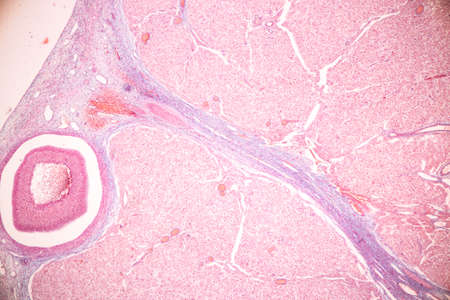

Low magnification of a human prostate gland in a 70-year-old man. The prostate gland appears with dilated alveoli, which contains many corpora amylacea (prostatic concretions) in their lumen. Light microscope micrograph. Hematoxylin & eosin stain.